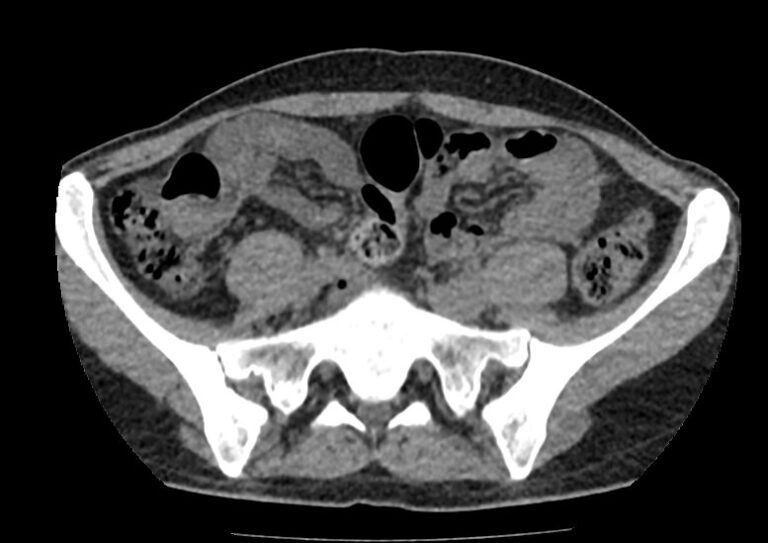

Мультиспиральная компьютерная томография позволяет детально оценить структуру лимфатических узлов, выявить ее неоднородность, определить точные размеры, выявить деформацию контуров, появление инфильтрации окружающих тканей с образованием цепочек, пакетов и конгломератов лимфоузлов.

Мультиспиральная компьютерная томография позволяет оценить структуру лимфатических узлов, обнаружить неоднородность, гиперплазию, деформацию их контуров.

Мультиспиральная компьютерная томография дает возможность визуализировать размеры лимфоузлов, их точную локализацию, взаимодействие с близлежащими органами и окружающими тканями, образование спаянных между собой инфильтратов лимфоузлов, выявить прорастание в окружающие ткани.

При проведении компьютерной томографии можно диагностировать следующие заболевания лимфатических узлов:

- Метастазы в лимфоузлах (поражение лимфатических узлов таза и подвздошных областей на фоне опухолей органов малого таза, брюшной полости;